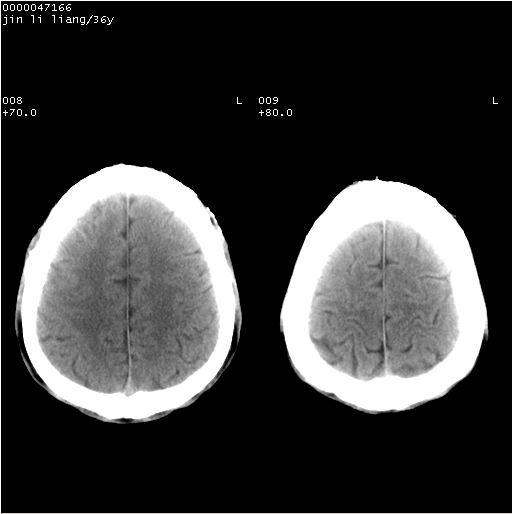

患者 男,36岁。头面部“土炮”炸伤。pe:面目全非,伤口流血不止。

临床诊断:头面部外伤。

颅脑ct轴位平扫(层厚、层距均为10mm),图像如下:

左眼球破裂并异物,眶周、额顶部头皮及软组织挫伤并异物

迎面一炮,满脸开曝。额顶部头皮及软组织挫伤并异物,左眼球破裂积气并异物,典型的面目全非,惨不忍睹。

左眼球破裂积气并异物,眶周、额顶部头皮及软组织挫伤并异物,右侧眼环前内分异物